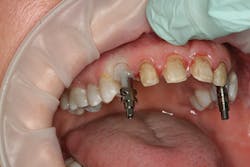

After approval of the diagnostic wax-up, profound anesthesia in the area of Nos. 6 through 11 was achieved (Septocaine, Septodont). Following sounding for bone to confirm adequate biologic width, laser soft-tissue recontouring in the areas of Nos. 6 through 11 was performed using an Er;Cr:YSGG soft- and hard-tissue laser (Waterlase, Biolase). Teeth Nos. 7, 8, 9, and 10 were prepared for conventional porcelain laminate veneers. Implant crowns were sectioned and removed from Nos. 6 and 11 (figure 4). To verify the radiographic implant identification, the abutments were removed and impression copings were tried in and radiographic seat was confirmed. The abutments were then replaced to serve as provisional restorative components. Screw access holes were blocked out and the provisional stent was used to fabricate provisional restorations on Nos. 6 through 11 (Luxatemp Ultra BL, DMG America) (figures 5, 6).

Figure 5

Figure 6